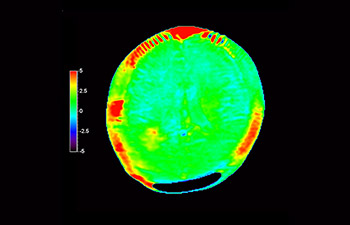

In una società in cui i disturbi neurologici rappresentano un grave problema, Philips si impegna a fornire una efficacia diagnostica senza pari e una guida per il trattamento di tutti i pazienti. Oggi, sebbene la risonanza magnetica sia lo standard di riferimento per l'imaging neuro-oncologico, è comunque possibile migliorarne la precisione nella definizione del grado del tumore e nelle valutazioni di follow-up della terapia. 3D APT (Amide Proton Transfer) è un esclusivo metodo di imaging RM del cervello senza contrasto che permette di ottenere diagnosi più affidabili nel campo della neuro-oncologia. Si avvale della presenza di proteine cellulari endogene per produrre un segnale RM direttamente correlato alla proliferazione delle cellule, un marker dell'attività tumorale. 3D APT è un valido supporto per il personale medico specializzato nella distinzione dei gliomi di grado basso e alto, e nella differenziazione della progressione del tumore rispetto agli effetti della terapia1.

con 3D APT